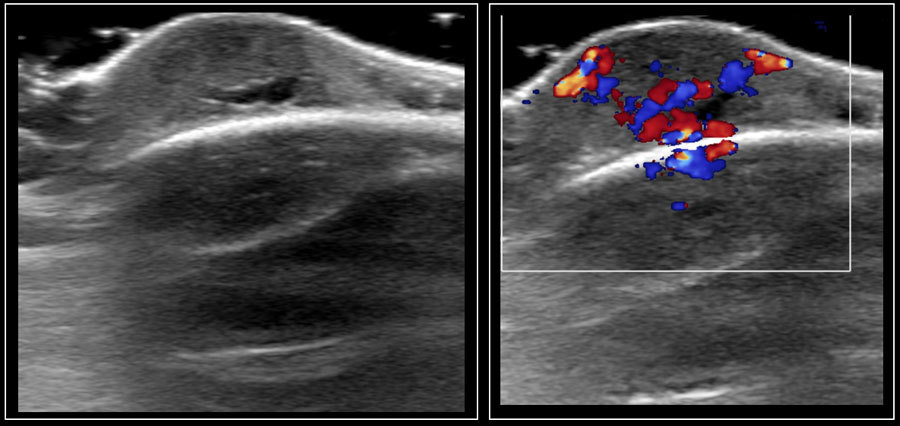

vascular paratesticular mass in a kiddo

think of?

Rhabdomyosarcoma

comes from epididymis or cord